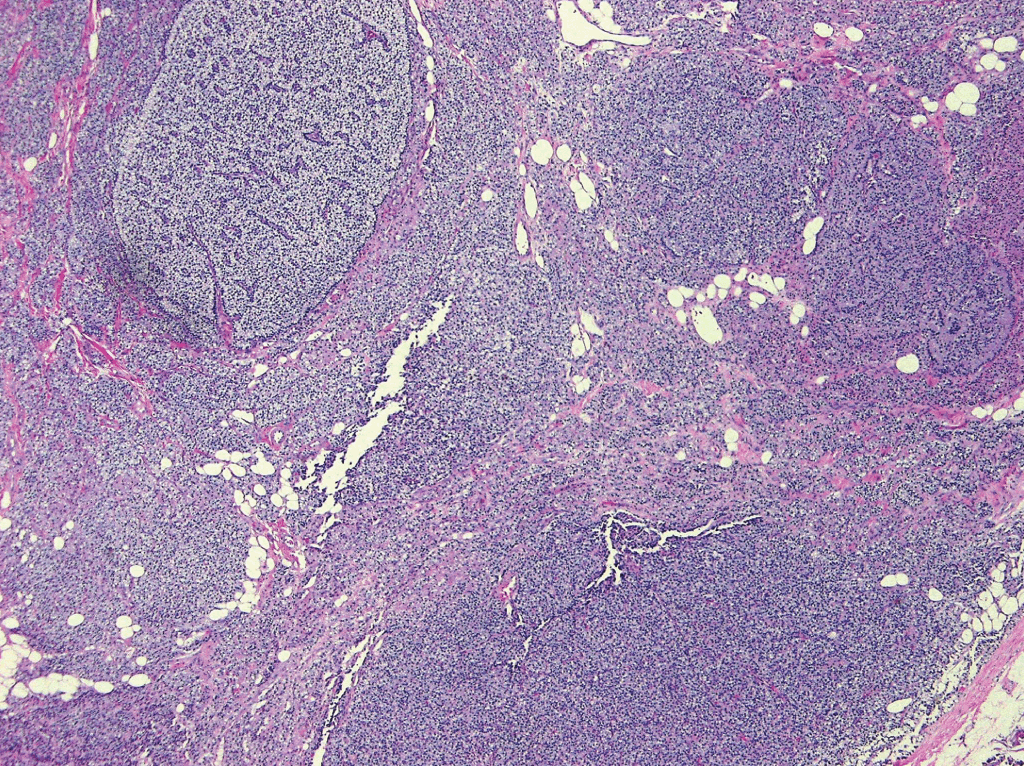

9b70fea5-1079-4abc-a0df-, Heptinstall's Pathology of the Kidney: 9781451144116,

Heptinstall's Pathology of the Kidney: 9781451144116, Heptinstall's Pathology of the Kidney: 9781451144116,

Heptinstall's Pathology of the Kidney: 9781451144116, Heptinstall's Pathology of the Kidney: 9781451144116,

Heptinstall's Pathology of the Kidney: 9781451144116, Renal Pathology of Ciliopathies - Thivya Sekar, Neil J,

Renal Pathology of Ciliopathies - Thivya Sekar, Neil J, Heptinstall's Pathology of the Kidney: 9781975161538,

Heptinstall's Pathology of the Kidney: 9781975161538, Non-neoplastic renal diseases (Chapter 31) - Silverberg's,

Non-neoplastic renal diseases (Chapter 31) - Silverberg's, The Aging Kidney and End-stage Renal Disease (Chapter 15,

The Aging Kidney and End-stage Renal Disease (Chapter 15, Renal Pathology of Ciliopathies - Thivya Sekar, Neil J,

Renal Pathology of Ciliopathies - Thivya Sekar, Neil J, Practical Approach to Congenital Anomalies of the Kidneys,

Practical Approach to Congenital Anomalies of the Kidneys, Cystic Diseases and Developmental Kidney Defects | Abdominal Key,

Cystic Diseases and Developmental Kidney Defects | Abdominal Key, The Aging Kidney and End-stage Renal Disease (Chapter 15,

The Aging Kidney and End-stage Renal Disease (Chapter 15, Tubulointerstitial Diseases (Chapter 12) - Silva's,

Tubulointerstitial Diseases (Chapter 12) - Silva's, Diagnostic Pathology: Kidney Diseases: 9780443107177

Diagnostic Pathology: Kidney Diseases: 9780443107177